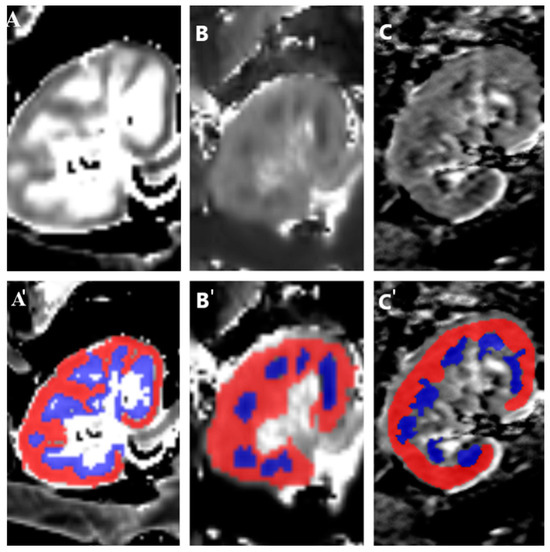

Two observers, a radiologist and a nephrologist, performed image analyses independently (Appendix B). Regions of interest (ROIs) for the cortex and medulla were delineated, ensuring uniform size and location for each region (Figure 1). Measurements were averaged across observers, and the mean and standard deviations for the cortex and medulla were calculated. Corticomedullary ratios (CMD) were computed to highlight relative differences between cortical and medullary values and normalize the data.

Figure 1.

The post-processing images of transplanted kidneys: T1 map (A), T2 map (B), and ADC map (C). Segmentation of renal MRI data. The cortex and medulla were identified map, and ROIs were semi-automatically delineated in the cortex (red) and medulla (blue) on the T1 map (A’), T2 map (B’), and ADC map (C’).

A radiologist and a nephrologist performed the image analyses. They evaluated T1, T2, and apparent diffusion coefficient (ADC) values in the middle section of the transplanted kidney in the coronal view. Each transplanted kidney was conditionally divided into three regions: upper, middle, and lower parts. For each patient, 8 regions of interest (ROIs) were drawn in these three parts for each kidney, targeting the cortex and medulla (Figure 1). The ROIs for the cortex and medulla had uniform sizes per region.

For T1 and T2 maps, which were acquired in the oblique coronal plane, ROIs were copied from the T1 maps into the corresponding slices in the T2 maps. Manual adjustments were made where regions between the T1 and T2 maps did not match. For ADC maps acquired in the axial plane, ROIs were manually adjusted on the cortical and medullary parts of the transplanted kidneys.